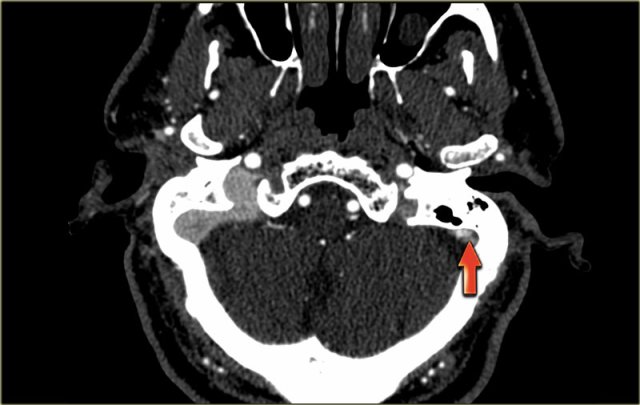

On the left images of a patient with a hemorrhagic infarction in the temporal lobe (red arrow).

Notice the dense transverse sinus due to thrombosis (blue arrows).

On the left images of a patient with hemorrhage in the temporal lobe.

When the hemorrhagic component of the infarction is large, it may look like any other intracerebral hematoma with surrounding vasogenic edema.

The clue to the diagnosis in this case is seen on the contrast enhanced image, which nicely demonstrates the filling defect in the sigmoid sinus (blue arrow).